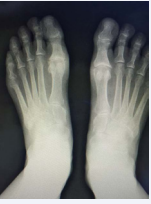

Before any treatments are offered a series of radiographs should be taken to assess the pathology of the first MPJ. This usually consists of the lateral, anteroposterior, and the medial oblique views of the affected foot. The AP view allows the practitioner to assess the joint space, while the lateral and MO views will show any associated spurring around the joint as well as the joint space. Occasionally loose bodies or sub chondral cysts are seen in any view taken. Sclerosis of the bone may also be seen on the radiographic studies since this is one of the ways that the bone tries to heal itself (Figure 1-4).

Figure 1: Pre operative Radiographs. This is a radiograph of a patient that presented to the clinic with a previous attempt at a 1st MPJ fusion that has failed. The patient elected to undergo a revisional procedure with the Arthrosurface total implant.

Figure 2: In this radiograph you can see the flattened appearance of the metatarsal head as well as significant joint space narrowing.